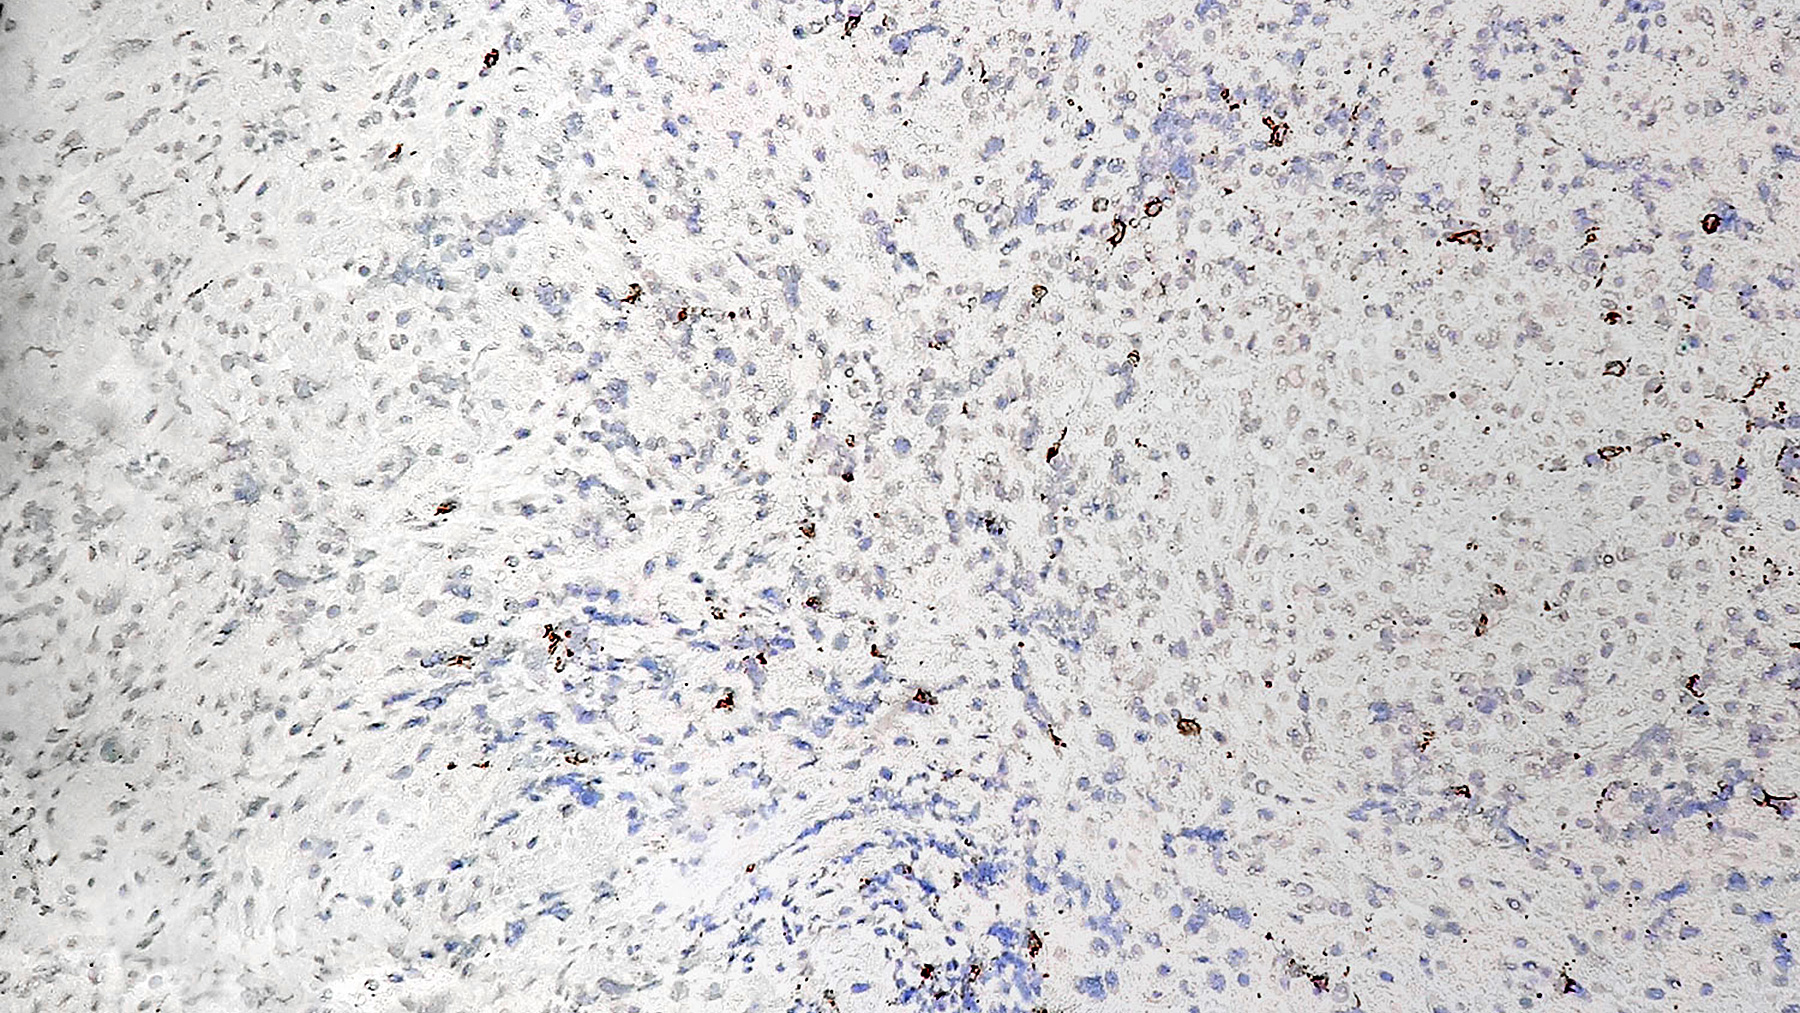

Figure B. CD3 IHC staining

Figure C. CD68 IHC staining

Histology: H&E section (Figure A) of the myocardial tissue shows foci of perivascular mononuclear cell infiltration with some associated myocardial damage consistent with moderate acute cellular rejection (grade 2R) (ISHLT 1990 Grade 3A).  Special immunohistochemistry staining for CD3 and CD68 (Figure B and Figure C) show a predominant population of T cells and macrophages. Special stating for CD20 shows only a few scattered B cells (Figure D).